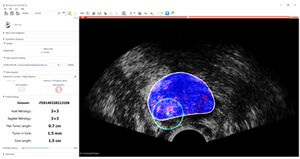

Publication: Int J Comput Assist Radiol Surg. 2018 Aug;13(8):1201-9. PMID: 29589258 | PDF Authors: Azizi S, Van Woudenberg N, Sojoudi S, Li M, Xu S, Abu Anas EM, Yan P, Tahmasebi A, Kwak JT, Turkbey B, Choyke P, Pinto P, Wood B, Mousavi P, Abolmaesumi P. Institution: The University of British Columbia, Vancouver, BC, Canada. Abstract: PURPOSE: We have previously proposed temporal enhanced ultrasound (TeUS) as a new paradigm for tissue characterization. TeUS is based on analyzing a sequence of ultrasound data with deep learning and has been demonstrated to be successful for detection of cancer in ultrasound-guided prostate biopsy. Our aim is to enable the dissemination of this technology to the community for large-scale clinical validation. METHODS: In this paper, we present a unified software framework demonstrating near-real-time analysis of ultrasound data stream using a deep learning solution. The system integrates ultrasound imaging hardware, visualization and a deep learning back-end to build an accessible, flexible and robust platform. A client-server approach is used in order to run computationally expensive algorithms in parallel. We demonstrate the efficacy of the framework using two applications as case studies. First, we show that prostate cancer detection using near-real-time analysis of RF and B-mode TeUS data and deep learning is feasible. Second, we present real-time segmentation of ultrasound prostate data using an integrated deep learning solution. RESULTS: The system is evaluated for cancer detection accuracy on ultrasound data obtained from a large clinical study with 255 biopsy cores from 157 subjects. It is further assessed with an independent dataset with 21 biopsy targets from six subjects. In the first study, we achieve area under the curve, sensitivity, specificity and accuracy of 0.94, 0.77, 0.94 and 0.92, respectively, for the detection of prostate cancer. In the second study, we achieve an AUC of 0.85. CONCLUSION: Our results suggest that TeUS-guided biopsy can be potentially effective for the detection of prostate cancer. |

Guidance interface implemented as part of a 3D Slicer module: cancer likelihood map is overlaid on B-mode ultrasound images. Red indicates predicted labels as cancer, and blue indicates predicted benign regions. The boundary of the segmented prostate is shown with white, and the green circle is centered around the target location which is shown in green dot. |